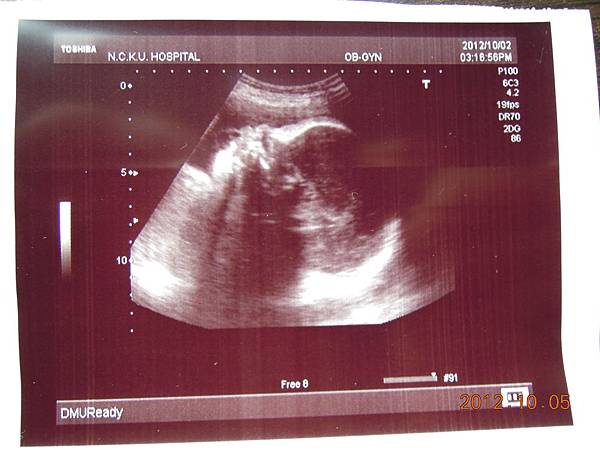

今天下午要做上次預約好的高層次超音波,一樣是到住院大樓四樓的超音波室等待~~

高層次超音波是用較精密儀器,並花較多時間仔細檢查胎兒的每一個部位和器官,所以還是把這兩千元花下去~

幫我檢查的應該是一位女醫師,這次檢查我媽也進去看,我記得上回檢查好像老公並沒有進去~不過上次是游醫師親自幫我做的檢查,今天因為游醫師剛好請假回來,掛號人數一定滿額,所以只好讓別的醫師服務囉~~

女醫師看起來超熟練,一邊照還會邊跟我解釋,這是逼逼的大腿,小腿,心臟,腎臟.....等等器官,一邊跟我媽聊天,說他生幾個....